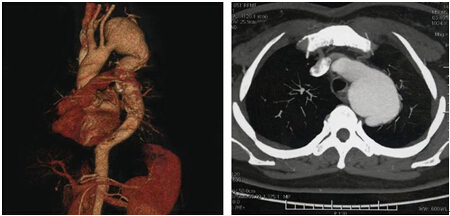

除夕歡慶夜,災(zāi)難不請自來

雞年除夕夜,正是萬家團(tuán)聚過新年的喜慶時(shí)刻。從江西趕來惠州和兒子一起過年的曾先生在吃飯時(shí)突然感到胸口一陣撕裂樣的劇烈疼痛,臉色蒼白,大汗淋漓,家人立即呼叫120。救護(hù)車一路呼嘯而過,直接開往惠州市第三人民醫(yī)院本部急診科。到達(dá)急診科后,醫(yī)院立即啟動(dòng)胸痛中心綠色通道,以最快速度完成主動(dòng)脈CTA檢查,并呼叫心內(nèi)科醫(yī)生。心內(nèi)科廖火城醫(yī)生一看CT,深深地倒吸了口冷氣……

很明顯,這是個(gè)巨大胸主動(dòng)脈瘤合并主動(dòng)脈夾層的患者,動(dòng)脈瘤隨時(shí)有破裂風(fēng)險(xiǎn),意味著患者一只腳已經(jīng)踏入了鬼門關(guān)。情況緊急,患者立即被轉(zhuǎn)入心內(nèi)科重癥監(jiān)護(hù)室,并在最短時(shí)間內(nèi)用藥物迅速控制了患者的胸痛癥狀,血壓和心率也趨于穩(wěn)定,病情暫時(shí)穩(wěn)定。

不幸的是,該患者在胸主動(dòng)脈瘤基礎(chǔ)上,又同時(shí)合并主動(dòng)脈夾層(也是主動(dòng)脈最為兇險(xiǎn)的疾?。?,病情就更為兇險(xiǎn)了,死亡率極高。

該患者雖經(jīng)積極藥物治療,病情趨于穩(wěn)定,但單純的藥物保守治療已不能有效阻斷動(dòng)脈瘤的破裂。既往治療該病的主要方法是通過切除動(dòng)脈瘤并用適當(dāng)大小的人造血管替換。但該手術(shù)過程較為復(fù)雜,創(chuàng)傷大、花費(fèi)多,而且危險(xiǎn)性也很高。

近年來,經(jīng)皮血管內(nèi)支架植入隔絕主動(dòng)脈瘤及主動(dòng)脈夾層破口的微創(chuàng)治療發(fā)展迅速,由于其創(chuàng)傷小、風(fēng)險(xiǎn)低、康復(fù)快,受到很多大醫(yī)院的青睞。

在肖純副院長指導(dǎo)下,由鐘思干主任、廖火城和劉建平醫(yī)生為核心的大血管團(tuán)隊(duì)經(jīng)過詳細(xì)的論證,最終決定為該患者實(shí)施支架植入的介入治療。歷時(shí)70余分鐘,以廖火城醫(yī)生為核心的大血管團(tuán)隊(duì)以精湛的技術(shù)為患者實(shí)施了胸主動(dòng)脈腔內(nèi)覆膜支架植入術(shù),主動(dòng)脈瘤合并夾層同時(shí)成功隔絕,且無大動(dòng)脈內(nèi)外瘺、截癱、腦梗塞、消化道出血等并發(fā)癥發(fā)生,患者體內(nèi)“定時(shí)炸彈”被成功拆除!